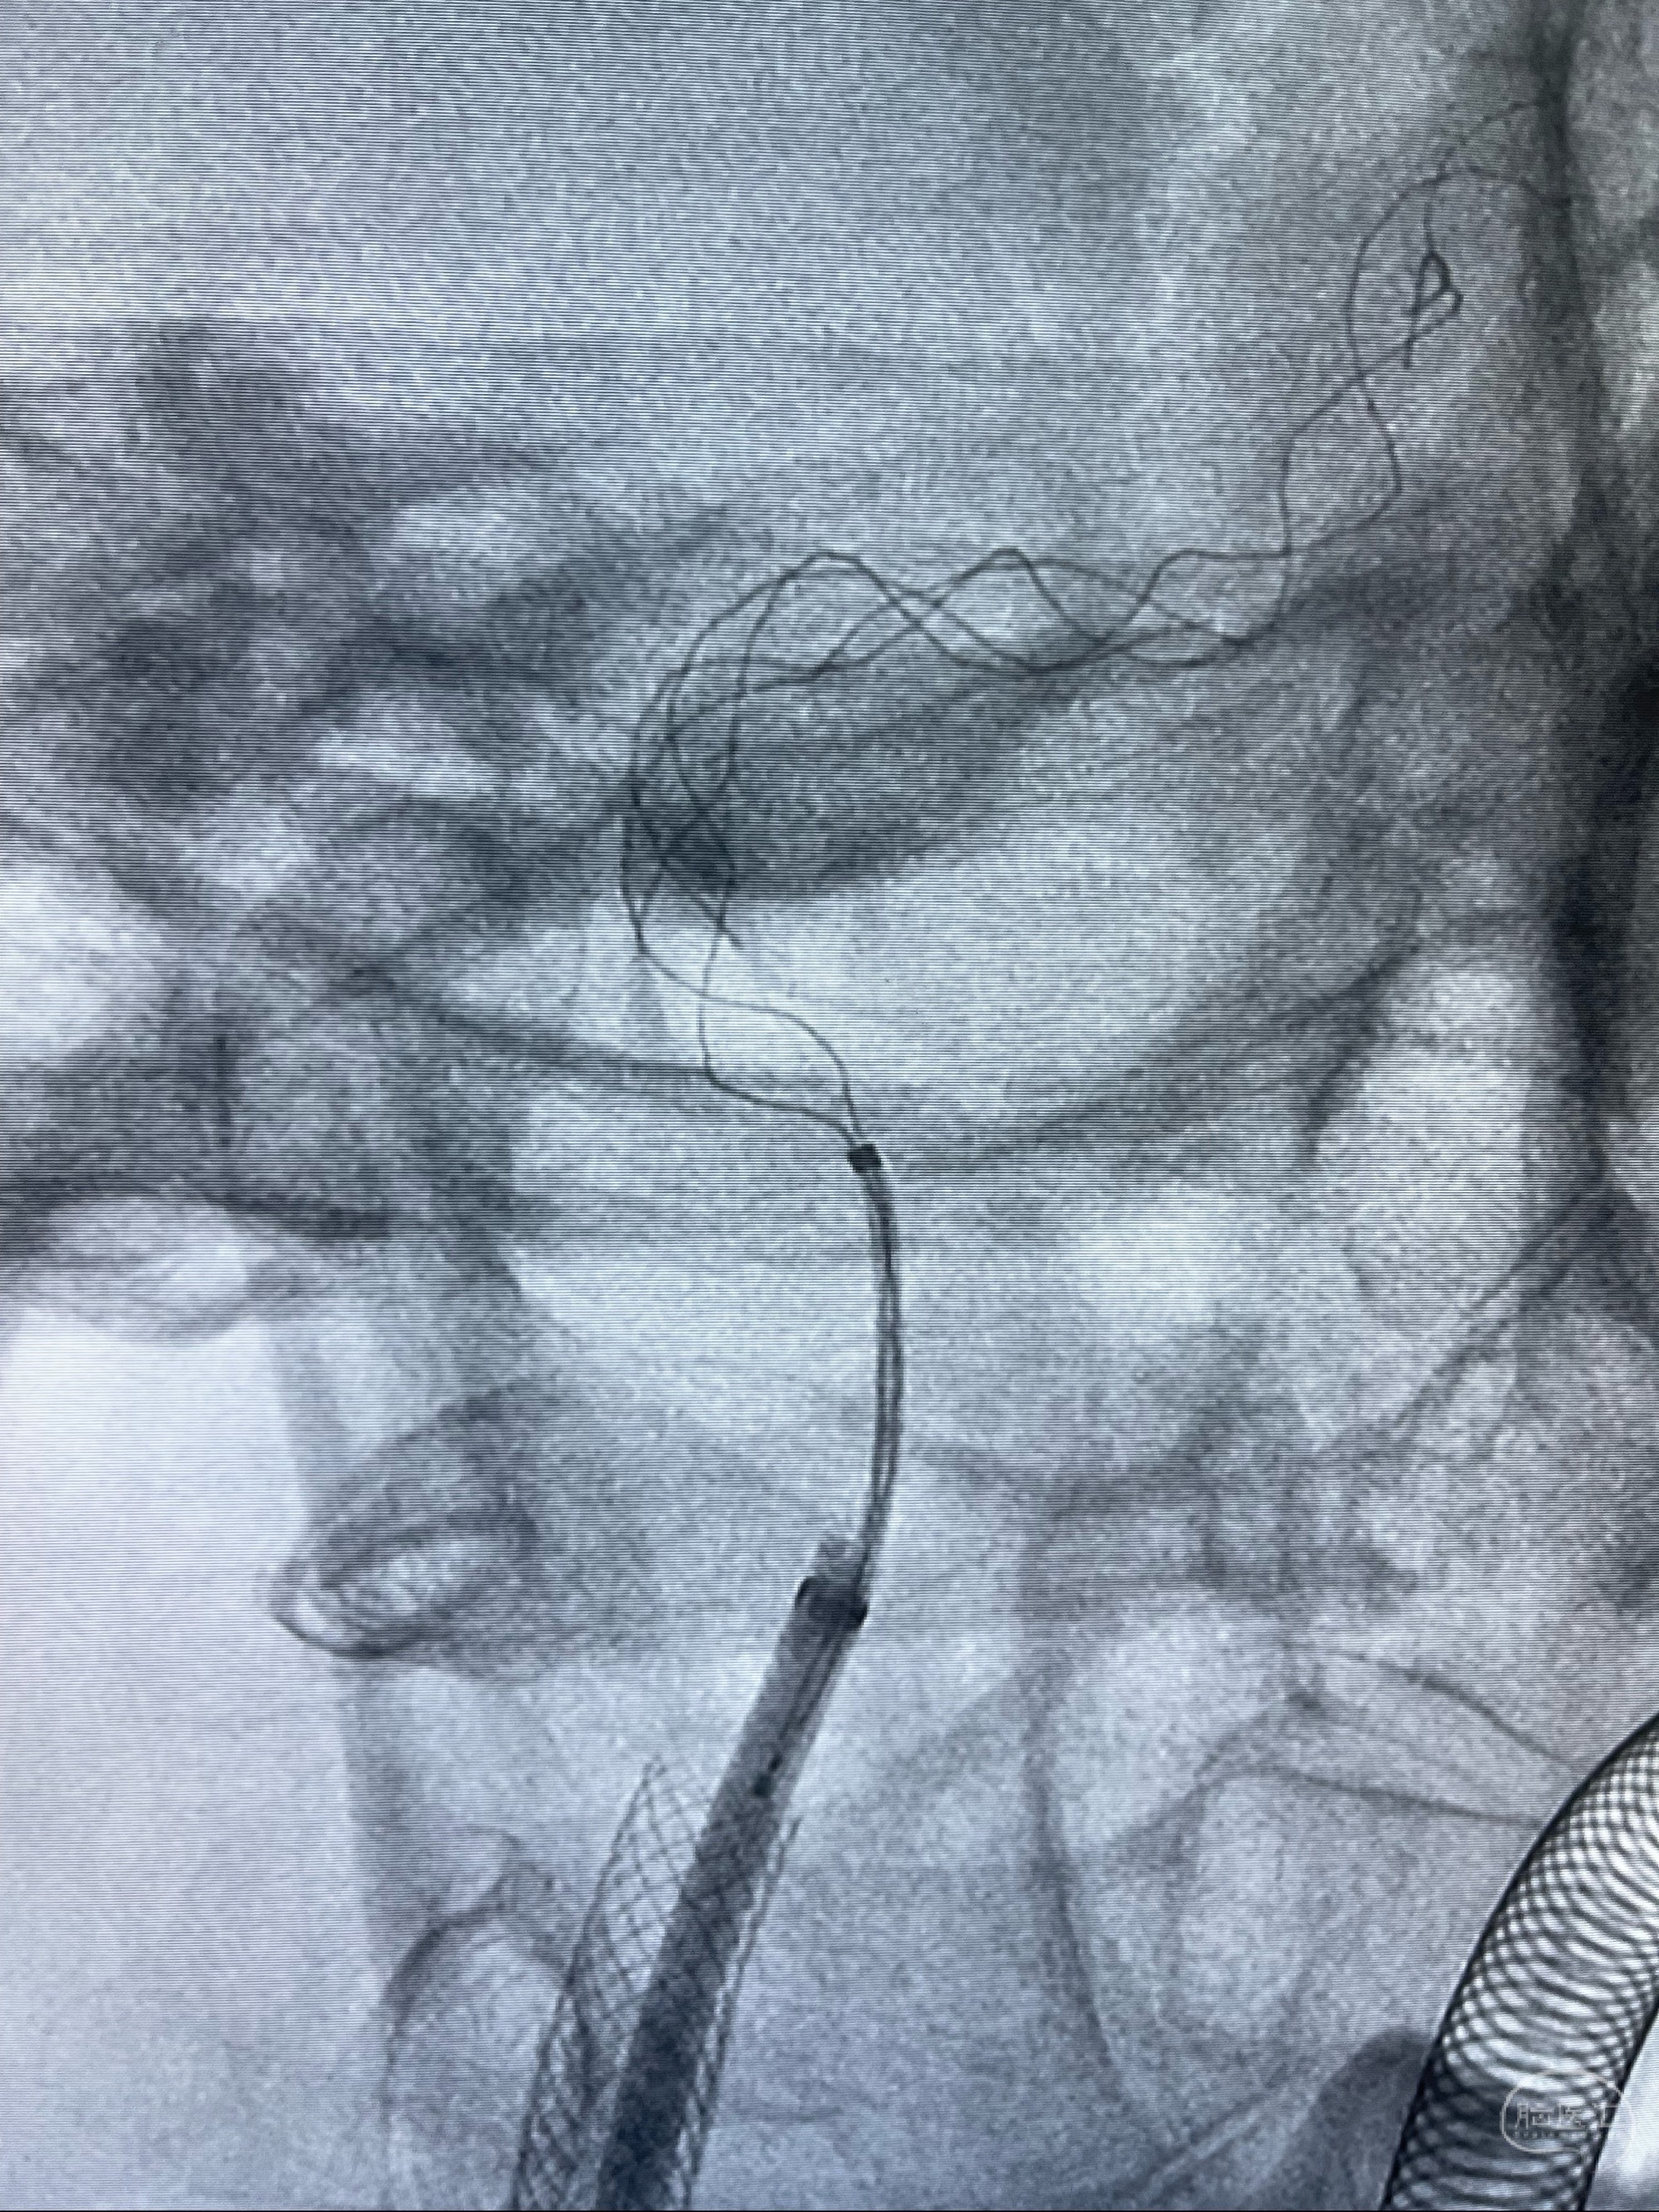

重新行“路径图”,支架导管在微导丝引导下超选择性插入至右侧颈内动脉眼段,4.5-50mmLeo支架释放,远心端位于海绵窦段,近心端位于岩骨段狭窄段以近

即刻造影显示支架贴壁佳

路径图下,5.5-50mmLeo支架导管在微导丝引导下超选择性插入远段Leo支架内

两枚支架部分重叠

多次确认支架位置及打开贴壁情况

支架完全打开,近心端位于原颈动脉支架远心端内